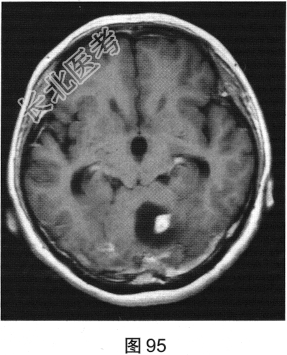

- 多项选择题2.[提示]患者行CT及MRI检查,如图90~图95所示。CT及MRI上的阳性影像学表现包括( )

A、MRI示右侧囊实性病变

B、病变实性成分增强扫描可见明显强化

C、MRI示左侧囊实性病变

D、MRI示右侧少许水肿

E、CT示左侧低密度灶

F、病变实性成分增强扫描未见明显强化

G、CT示右侧低密度灶

H、MRI示左侧少许水肿